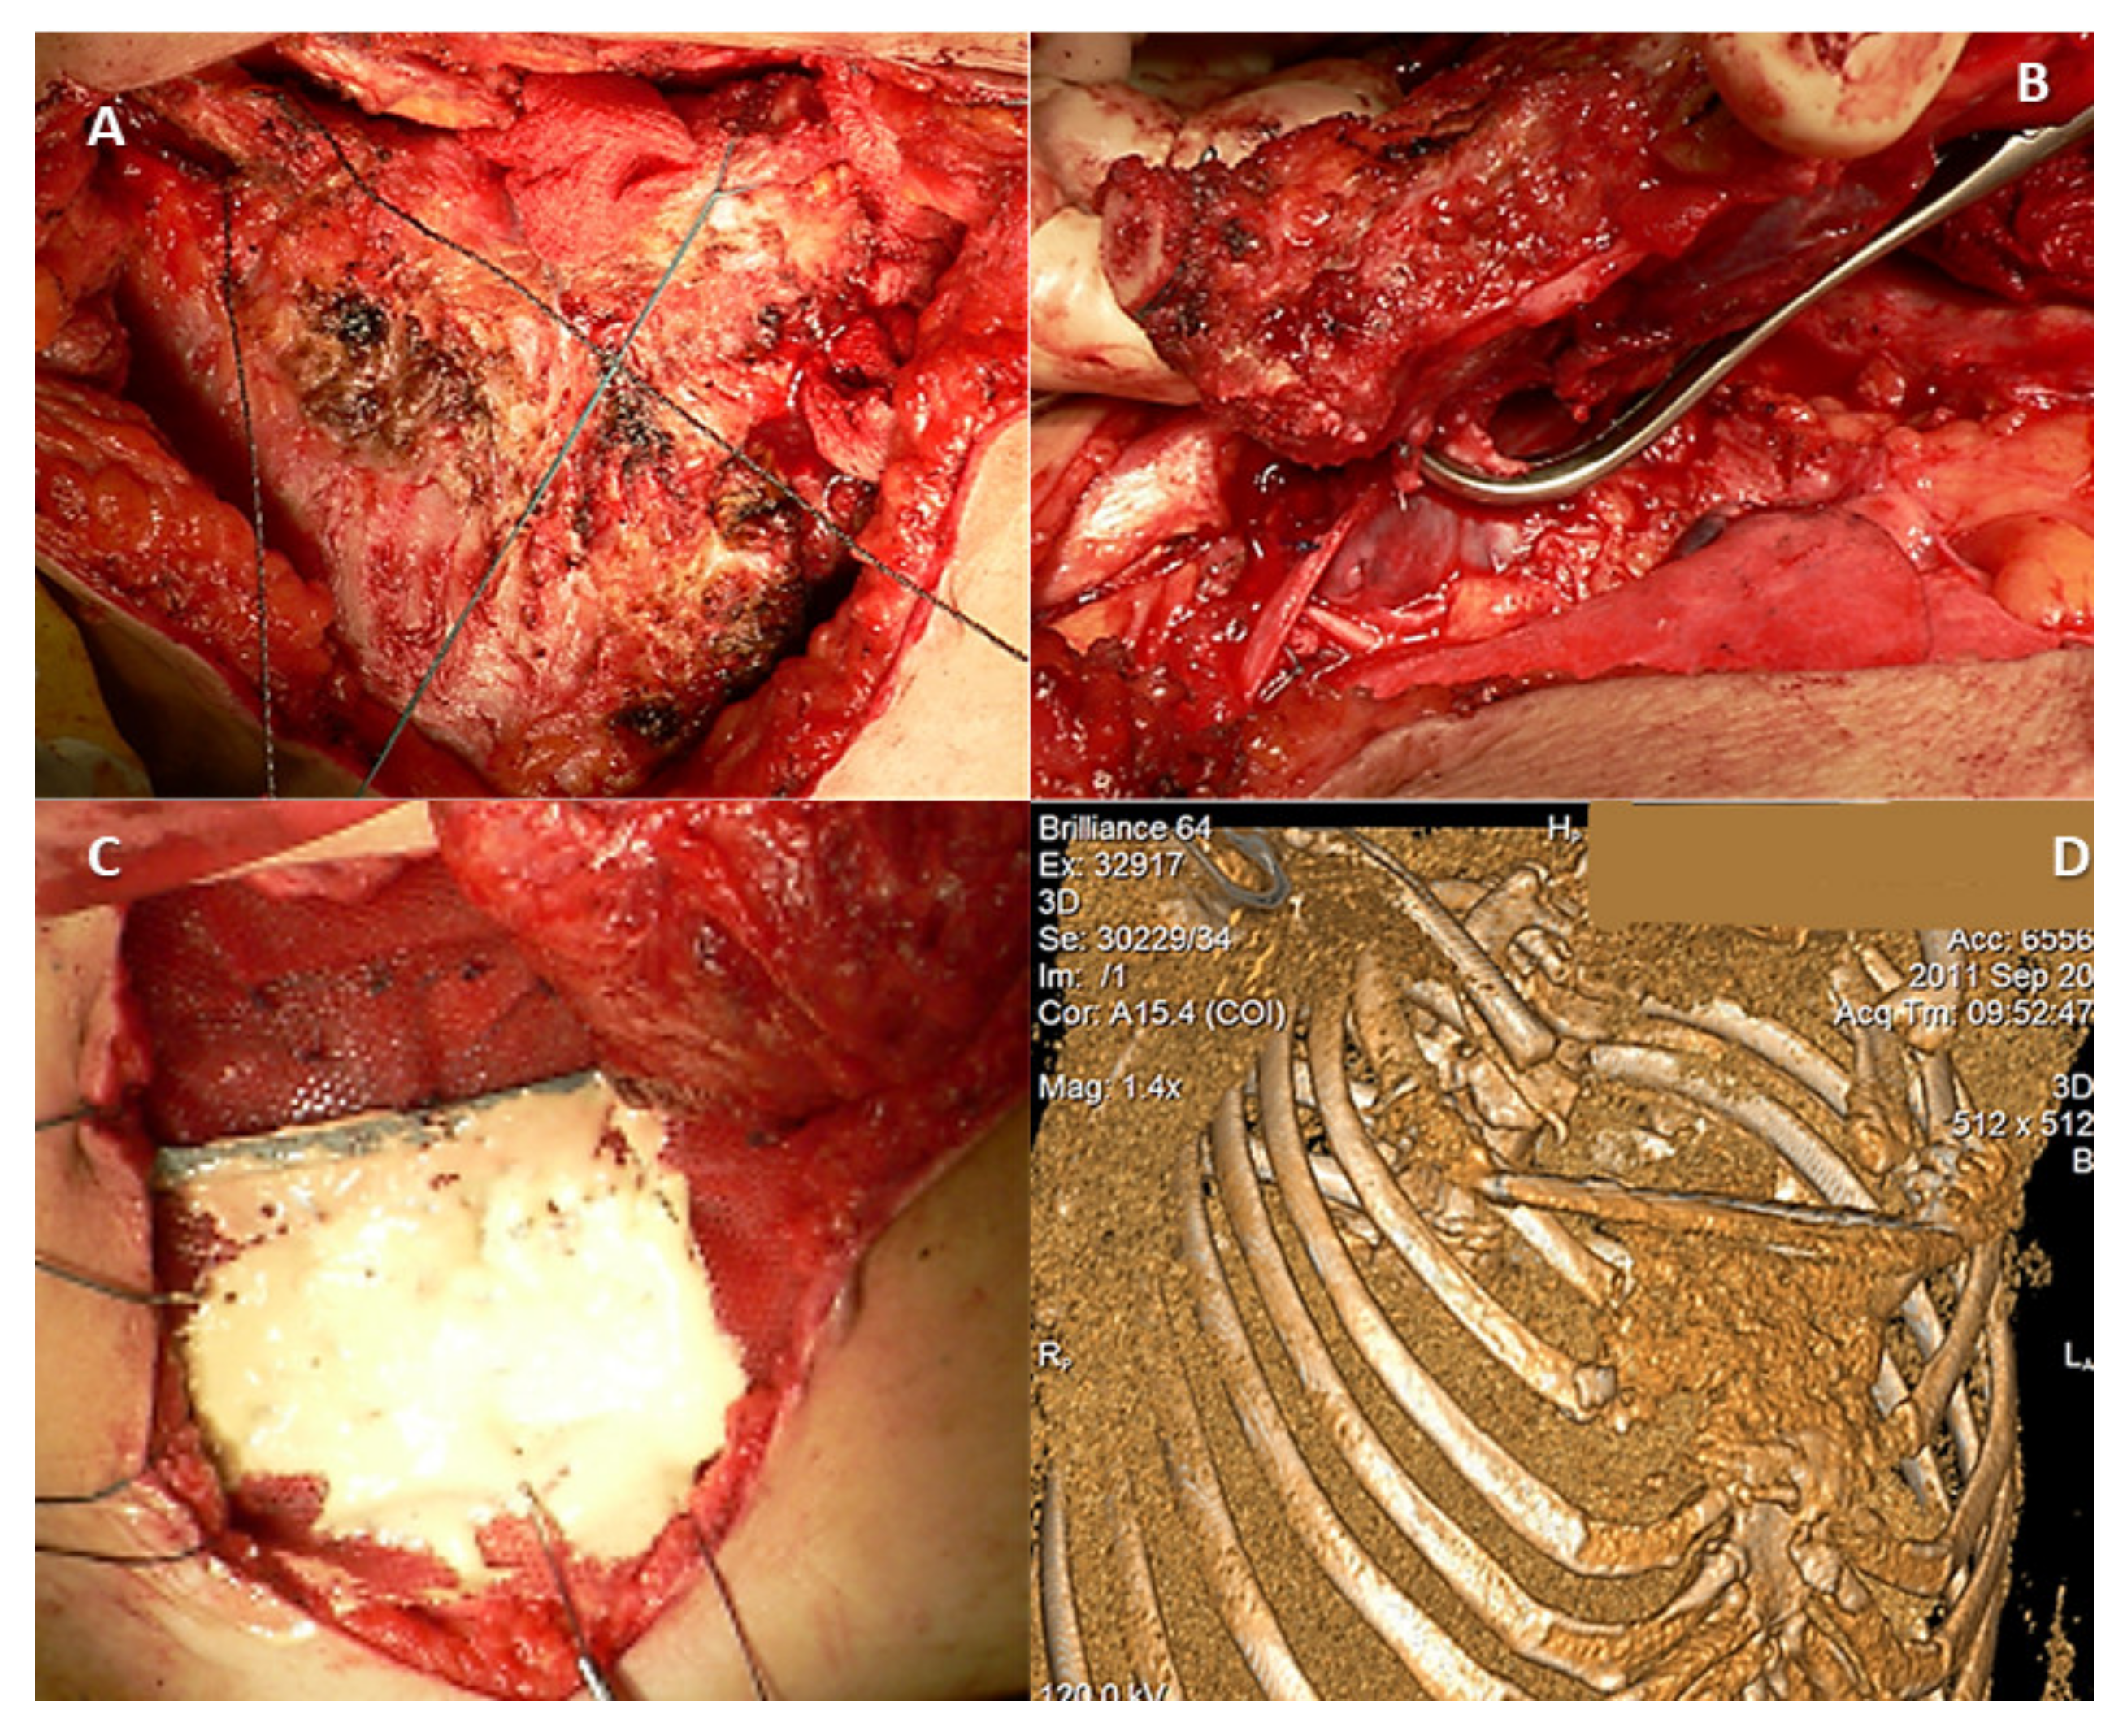

Figure 2.

(A) Preoperative tomography of a 66-year-old male diagnosed with clavicle condrosarcoma. (B) Preoperative angiography and embolization of the tumor were performed prior to resection to limit intraoperative blood loss. (C) Postoperative image of acrylic cement reinforced with Kirschner brooches reconstruction used after tumoral resection.

Partial or complete claviculectomy involves substantial peri-operative risks, such as lesions of the subclavian plexus or the brachial plexus, as well as infectious risks [29,30,31]. Post-resection reconstruction of the partial or total claviculectomy is important for several reasons—including maintaining the biomechanics of the scapular girdle, protecting the vessels and nerves, reducing pain, and maintaining the anatomical appearance of the shoulder. One reconstructive method following a complete resection of the clavicle is with a vascularized autograft fibula or rib, and several case reports describe the surgical technique but without comparing claviculectomy with reconstructive procedures [32,33,34]. Alternative reconstruction options involve acrylic cement reinforced with plate and screws or with Kirschner brooches, which may avoid possible complications secondary to complete resection of the collarbone (Figure 2). After reviewing five cases treated with this procedure, the authors concluded that bone cement prosthesis for bone defect reconstruction after tumor resection can maintain the contour of the shoulder and reduce the complications ascribed to the claviculectomy, and the procedure is effective and feasible [35]. Moreover, the “Oklahoma prosthesis” reconstructive method, with a cement allograft, has been successfully used to maintain the biomechanical integrity of the scapular girdle in cases of clavicular middle third secondary tumors that invade the sternum and rib. The technique consists of an en bloc clavilculectomy and chest wall resection with a method of reconstruction using a single methyl methacrylate and prolene composite prosthesis in a configuration resembling the state of Oklahoma [36].